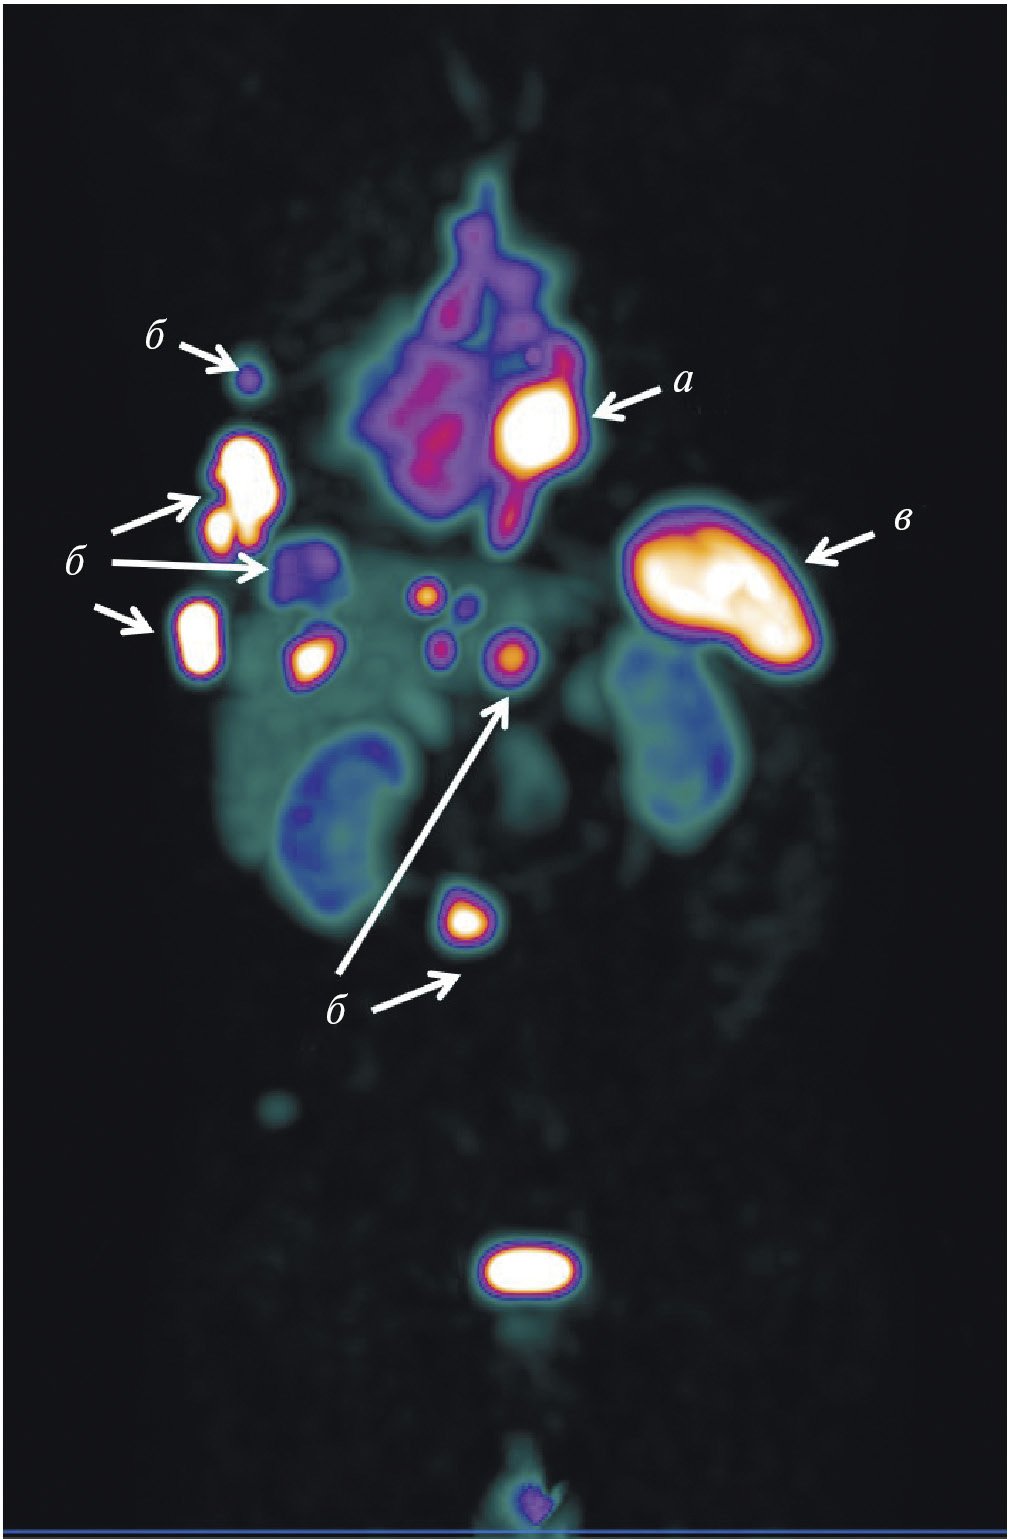

Рис. 1. ПЭТ-изображение пациентки с HER2/neu-позитивным раком молочной железы, выполненное через 5 суток после введения 89Zr-транстузумаба (a), стрелками обозначены метастазы в печень и кости [12]; ОФЭКТ-изображение пациентки с HER2/neu-позитивным раком молочной железы через 2 ч после введения 99mTc-ADAPT6 (б), стрелками обозначены первичная опухоль, метастазы в лимфатические узлы, печень и кости

Рис. 3. ОФЭКТ/КТ с 99mТс-октреотидом пациента с нейроэндокринным раком лёгкого: а — конгломерат первичной опухоли и метастазов в лимфатические узлы; б — метастазы в кости; в – селезёнка

Рис. 4. ОФЭКТ с 99mТс-ПСМА пациента с раком простаты до (а) и после (б) четырёх курсов радиолигандной терапии 177Lu-ПСМА